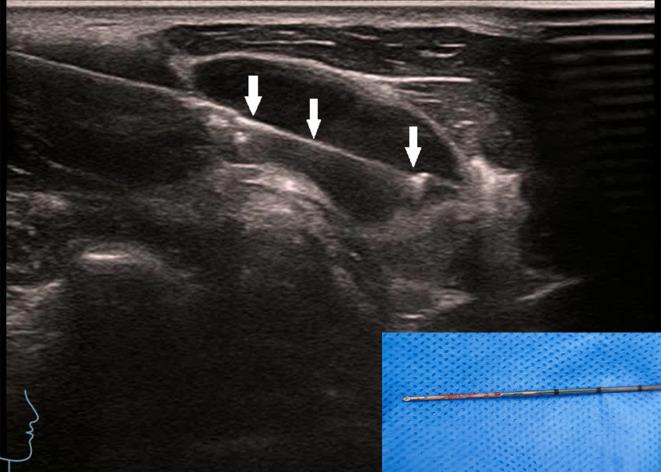

To investigate the value of contrast-enhanced ultrasound (CEUS) assisted core needle biopsy (CNB) in the diagnosis of cervical lymph node tuberculosis (LN TB) and improve the positive rate of cervical LN TB.

We retrospectively analyzed 730 samples obtained from July 2010 to January 2025 from patients treated with effective antituberculosis therapy and with microbiologically confirmed and surgical pathologically proven cervical lymph node enlargement who had undergone CEUS- CNB at our hospital. All patients were divided into two groups according to the historical control method. The CEUS group (2017-2025) underwent CEUS- CNB (485 cases), whereas the US group (2010-2018) underwent US-guided CNB (245 cases). The positive rates of pathological diagnosis and Xpert Mycobacterium tuberculosis complex (MTBC) and resistance to rifampin (RIF) (MTB/RIF) assay diagnoses were compared between the groups.

The specimens' integrity was significantly higher after CNB in the CEUS group than in the US group (CEUS group: 72.30%; US group: 45.49%), and visual satisfaction of sampling in the CEUS group was higher (χ2: 47.651, P < 0.001). Histopathological examination sensitivity, specificity, positive predictive value, and negative predictive value were higher in the CEUS group than in the US group. The sensitivity of the Xpert MTB/RIF assay was significantly higher in the CEUS group than in the US group.

The study results support the clinical use of CEUS for improving the diagnostic performance and positive rate for cervical LN TB.